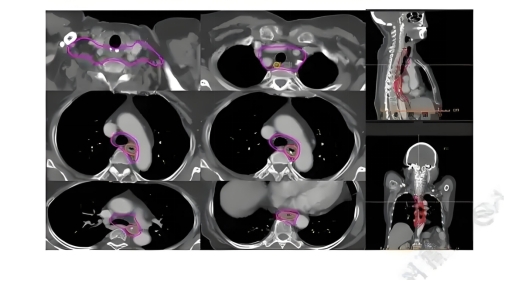

• 定位期:定制身体固定模具,通过CT/PET影像勾画肿瘤靶区。

• 计划期:医生计算剂量方案,确保射线聚焦肿瘤,避开健康组织。